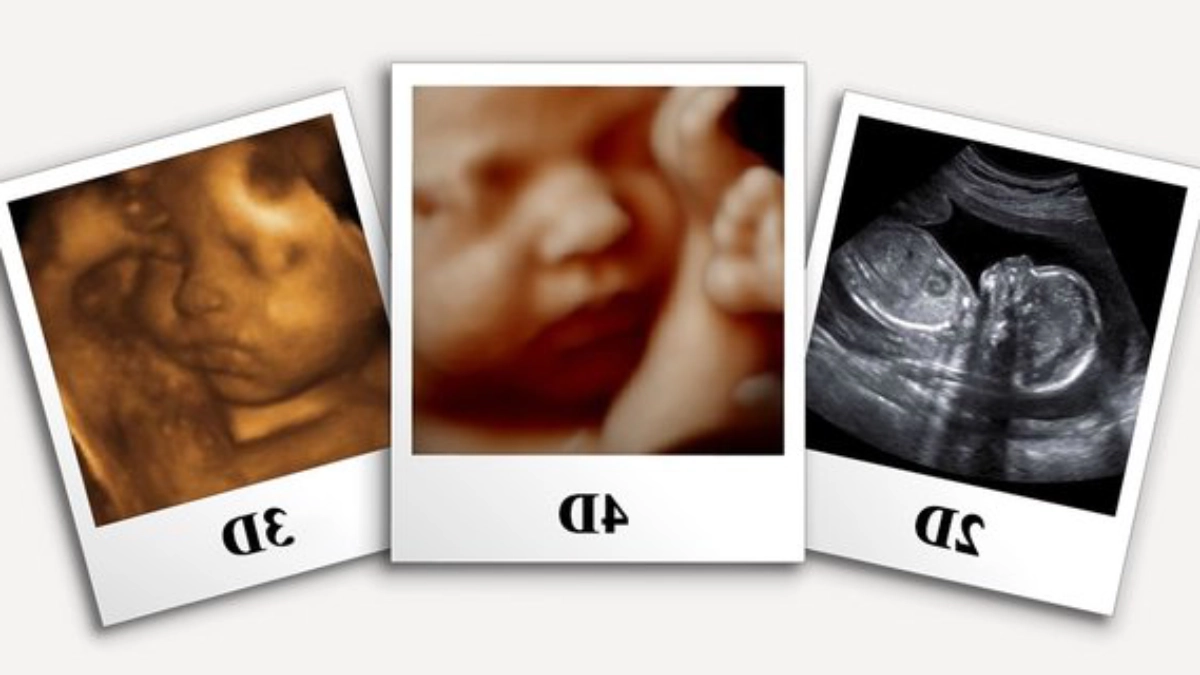

سونوگرافی 2 بعدی تصاویری سیاه و سفید و مسطح از جنین ارائه میدهد که بیشتر برای شناسایی مشکلات داخلی مانند نقص قلب یا کلیه استفاده میشود.

سونوگرافی 3 بعدی تصاویری سهبعدی از جنین ارائه میکند که امکان مشاهده ساختارهای سطحی مانند صورت و دستها را فراهم میکند.

در مقابل، سونوگرافی 4 بعدی تصاویر زنده و متحرک از جنین ارائه میدهد که بهویژه برای والدینی که میخواهند حرکات جنین را مشاهده کنند، جذابیت بیشتری دارد.